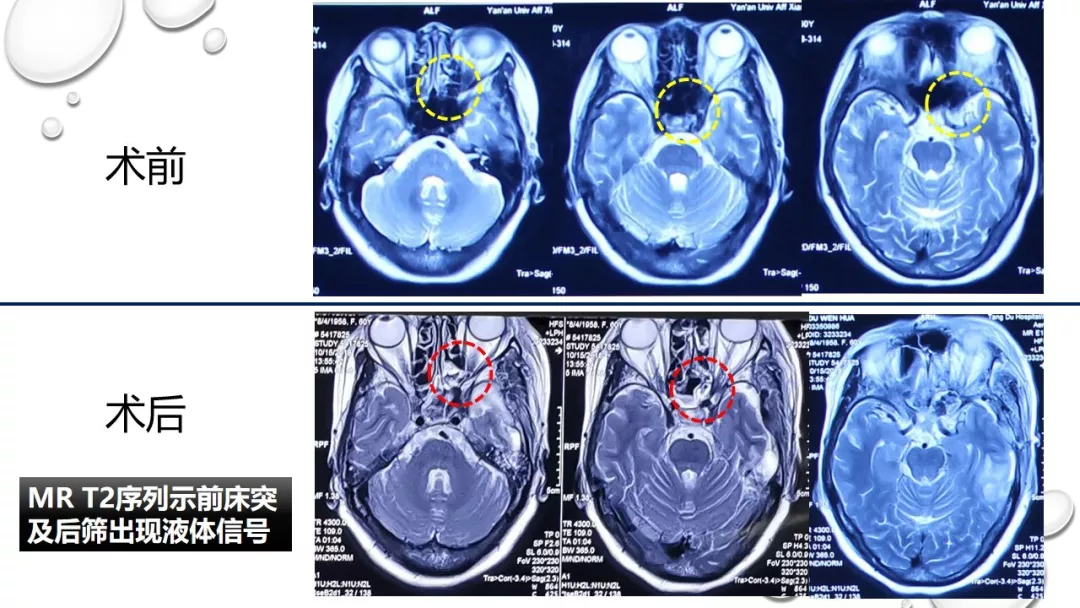

今日与大家分享的是《正海-妙术视界》第一百三十二期,由唐都医院神经外科赵天智、郭为、贺世明、屈延、高国栋带来的精彩手术:“前床突磨除与脑脊液漏处理---中鼻道经筛入路解剖、阅片与手术”,欢迎观看、分享。

内镜修补